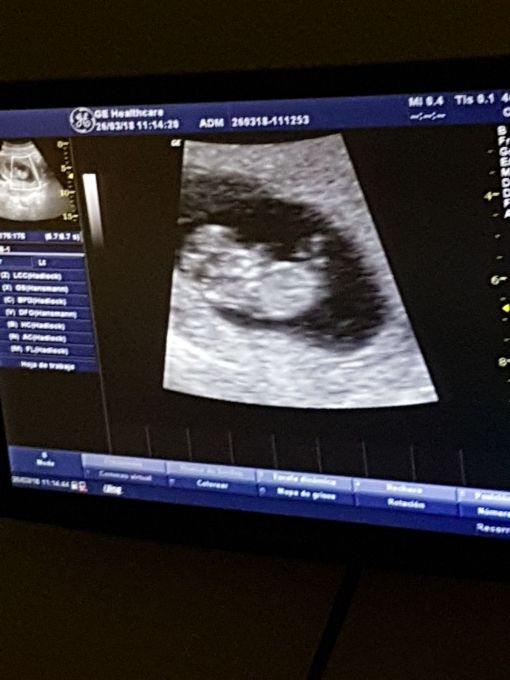

Agora que os três meses iniciais vulgo “de perigo” passaram, assim como os enjôos; agora que pude ver por duas vezes com meus próprios olhos que havia um outro ser dentro da minha barriga e pude ouvir seu coração bater aceleradamente; agora que através de vários exames me foi afirmado por diversas vezes que está tudo como deveria ser, posso comunicar oficialmente que seremos pais! Digo, eu já me considero mãe desde que vi o primeiro teste de farmácia resultar positivo, mas se for de acordo com o ditado “mãe/pai é quem cuida/cria”, então os títulos só poderão ser utilizados a partir do meio de outubro (o nascimento está estimado +- para o dia 18).

Não estou com pressa, nem tampouco querendo que o tempo pare, cada dia tem sido um dia especial, como todos deveriam ser. Tenho me cercado de boa literatura, de boa música, de muito amor, atenção e carinho. Acho que dentre os dias de maior exaltação emocional que tive desde a concepção, eu classificaria como o número 1 ver o resultado positivo do teste de farmácia, número 2 assistir ao primeiro ultra-som e número 3 o segundo ultra-som. É muito engraçado como nunca estou 100% convicta e segura do que acontece comigo, mas nessas 3 ocasiões por um breve momento tive esses estados de exaltação que nunca saberia colocar em palavras.